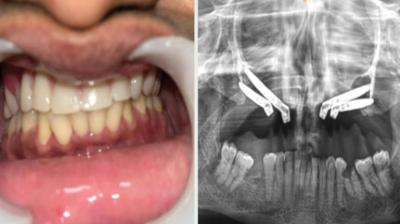

एम्स भोपाल में जटिल सर्जरी सफल, युवती को मिला नया जीवन

6 Sep, 2025 10:00 PM IST | SKNEWS.CO.IN

एम्म में जटिल सर्जरी को सफलतापूर्वक अंजाम दिया है। इस सर्जरी में ट्यूमर के कारण काटे गए निचले जबड़े को पैर की हड्डी से दोबारा बनाया गया और उसमें 13...